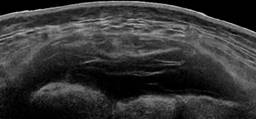

En radiografías simples de pelvis se identificó una fractura de la rama inferior de pubis izquierdo, el ultrasonido (USG) de tejidos blandos reveló una acumulación de líquido hipoecogénico entre el tejido celular subcutáneo y la fascia con dimensiones de 14 × 60 × 95 centímetros para un volumen de 426 ml, lo que indicaba una posible LML lumbar (Figura 1). La tomografía reveló una colección de líquido hipodenso, unilocular, entre la fascia y el tejido celular subcutáneo, con un volumen similar.

Figura 1: Ecografía de partes blandas que muestra colección entre la fascia y el tejido celular subcutáneo de región sacra.

El diagnóstico de este tipo de lesiones se basa principalmente en el examen físico, algunos signos y síntomas pueden ser variables y elusivos, quemaduras por fricción y escoriaciones en la región lumbar pueden ser pistas para el diagnóstico. La hipermovilidad de la piel es otro signo clínico útil, en especial cuando el paciente presenta varios días después del trauma. La pérdida de la sensibilidad cutánea sobre el área lesionada puede ser consecuencia de cizallamiento de los nervios cutáneos. Una vez establecido el diagnóstico clínico se puede respaldar mediante estudios de imagen, el USG ofrece una manera rápida y accesible de establecer el diagnóstico, como se describió en nuestro caso. El USG puede mostrar una colección de líquido entre la fascia y el tejido celular subcutáneo, por lo general hipoecogénico y unilocular si se realiza en la fase aguda, esto puede cambiar con la cronicidad de la lesión, la cual se puede volver multilocular. Por otro lado, la resonancia magnética (RM) es el estudio de elección. Típicamente esta lesión se presenta como una colección de fluido entre las capas antes descritas, con aspectos variables en la RM, principalmente dependiendo en el tiempo transcurrido entre el trauma inicial y la cantidad de sangre, grasa y tejido linfático que se encuentre en él. Posteriormente, la presencia en T1 y T2 de un anillo concéntrico hipointenso que realza al gadolinio, sugiere fuertemente la presencia de una pseudocápsula que puede evitar la reabsorción del contenido. Mellado y colaboradores describen seis tipos de LML basadas en la forma de la lesión, presencia o ausencia de cápsula y características en la RM, así como signos de mejoría (Tabla 1).10 Los radiólogos deben conocer estos hallazgos de la RM para ayudar a los clínicos en el diagnóstico y elegir la mejor opción terapéutica. Además, el realce ocasional del gadolinio ha llevado a los radiólogos a confundirlo con un sarcoma de tejidos blandos como en el caso reportado por Zairi y colegas.11 La localización característica y la historia de trauma pueden ayudar a distinguir una LML de una neoplasia.